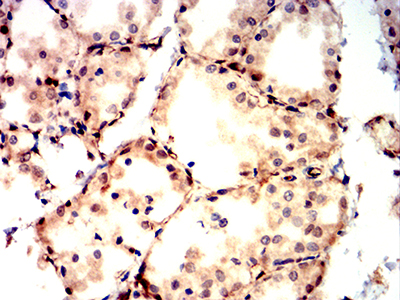

Immunohistochemical analysis of paraffin-embedded Rat kidney using BAX mouse mAb with DAB staining.